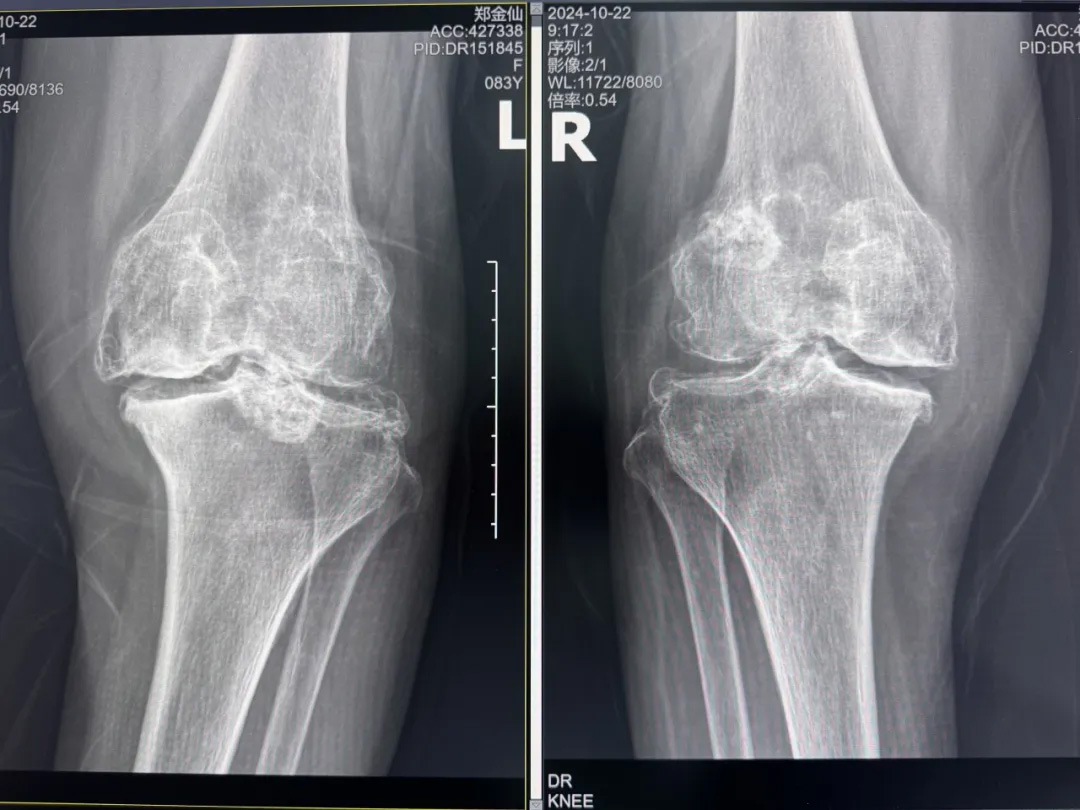

年輕時愛到處走走的鄭阿婆,晚年卻被雙膝劇痛困在輪椅上長達(dá)二十年。經(jīng)羅副院長診斷,她的膝關(guān)節(jié)軟骨幾乎磨光,關(guān)節(jié)嚴(yán)重畸形,呈"羅圈腿",走幾步便疼痛鉆心,連如廁都需家人抱扶。“我這輩子啊,估計再也站不起來了。”是阿婆最常說的話。